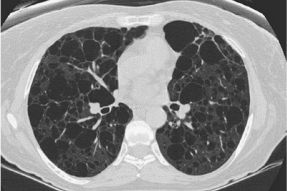

比如淋巴管肌瘤病(LAM),下图是典型影像,呈现弥漫性的薄壁囊肿,病变分布得非常均匀、大小相似:

图:淋巴管肌瘤病,TSC相关(结节性硬化症,一种多系统表现的肿瘤性遗传病)